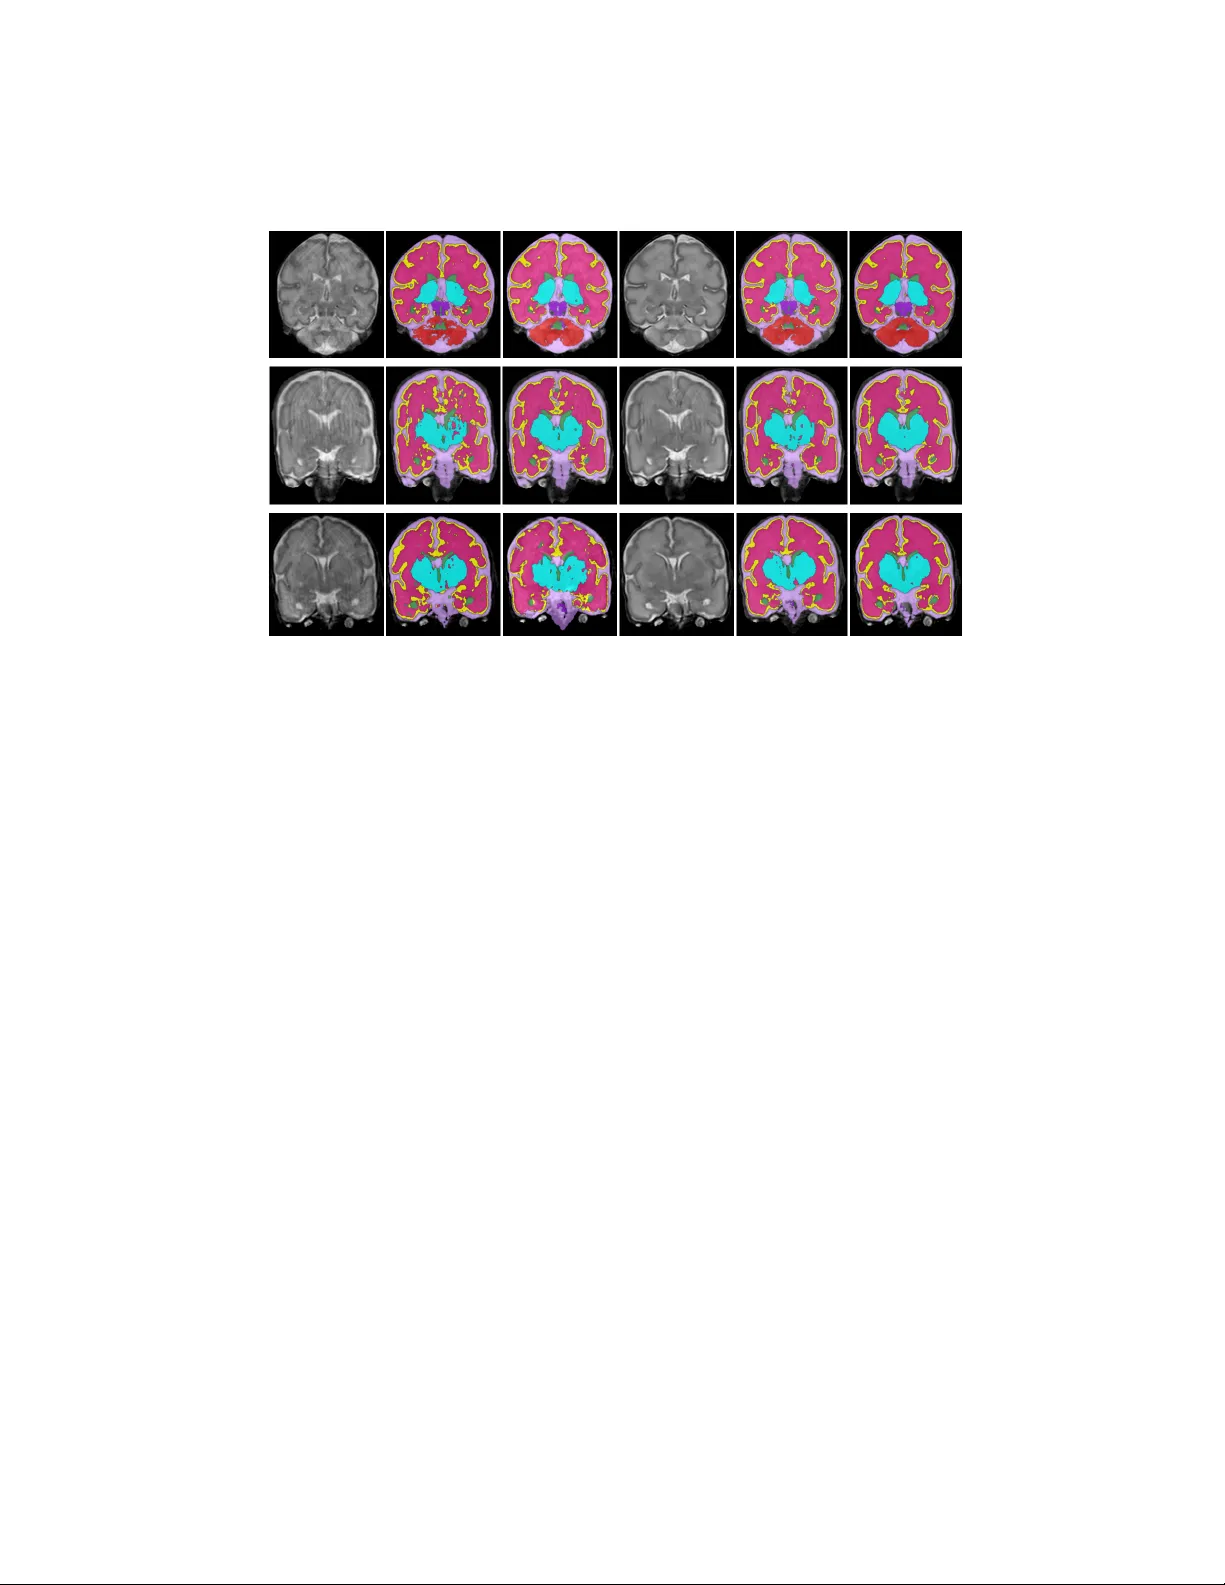

결과는 다음과 같다. 무모션 이미지에 대한 최상위 세분화 성능은 Dice 평균 0.90, HD 44.9 mm, MSD 0.36 mm였다. 모션이 합성된 이미지에서는 Dice가 0.87, HD 52.3 mm, MSD 0.62 mm로 감소했지만, MC를 적용해 교정한 후에는 Dice가 0.90, HD 45.1 mm, MSD 0.46 mm로 회복되었다. 데이터 증강(무모션 이미지에 MG로 합성한 모션 이미지 포함)으로 훈련한 세분화 모델은 Dice가 0.91, HD 45.6 mm, MSD 0.45 mm까지 향상되었다. 주관적 평가에서도 이미지 품질이 2→3점, 세분화 품질이 3→4점으로 각각 향상되었다.

성능 평가는 두 가지 방식으로 진행되었다. 첫째, MG를 이용해 무모션 이미지에 인위적으로 모션을 합성하고, 해당 합성 이미지에 대해 수동 라벨을 이용해 Dice, Hausdorff distance, Mean surface distance를 측정했다. 둘째, 실제 모션이 있는 40개 스캔에 MC를 적용한 후, 교정 전후 이미지와 자동 세분화 결과를 5점 Likert 척도로 주관적 평가했다.